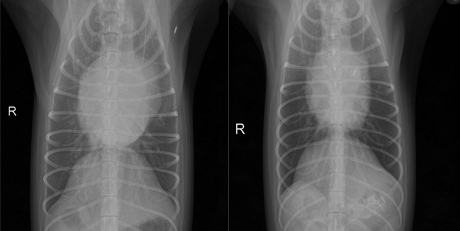

1. 심혈관중재치료

심혈관 중재치료란 대퇴동맥/경정맥 혈관 접근으로 심장의 구조 이상을 교정/치료하거나 심장 사상충 중감염 환자에서 약물치료가 위험하거나 불가능한 경우 사상충을 직접 제거하는 등 혈관을 경유하여 심장과 관련된 문제점을 치료하는 것입니다. 일반적인 개흉수술에 비하여 환자의 회복속도가 매우 빠르며, 합병증도 최소화 할 수 있는 장점이 있습니다.